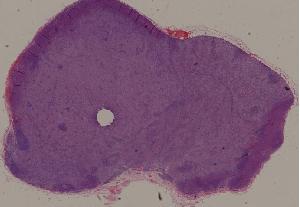

23.炎性息肉